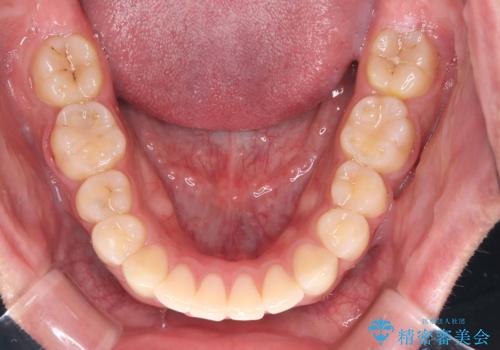

- 咬み合わせの不調和と歯並びのデコボコを主訴にご来院された患者様です。

精密矯正検査の結果、歯を抜かずに非抜歯でワイヤー矯正で治療を行う方針としました。

叢生(歯のデコボコ)の量が多く、加えてディープバイト(過蓋咬合)や重度の捻転も認められたため、リンガルアーチやマイクロインプラントなどの補助装置を併用し、治療を進めました。

治療途中では咬み合わせの改善を目的としてバイトアップを行い、歯の捻転や叢生を改善しつつ、機能的に安定した咬合を獲得しています。

上顎左右4番は90度捻転していたため、改善後歯根露出してしまっているためCTG(歯肉移植)を行う予定です。